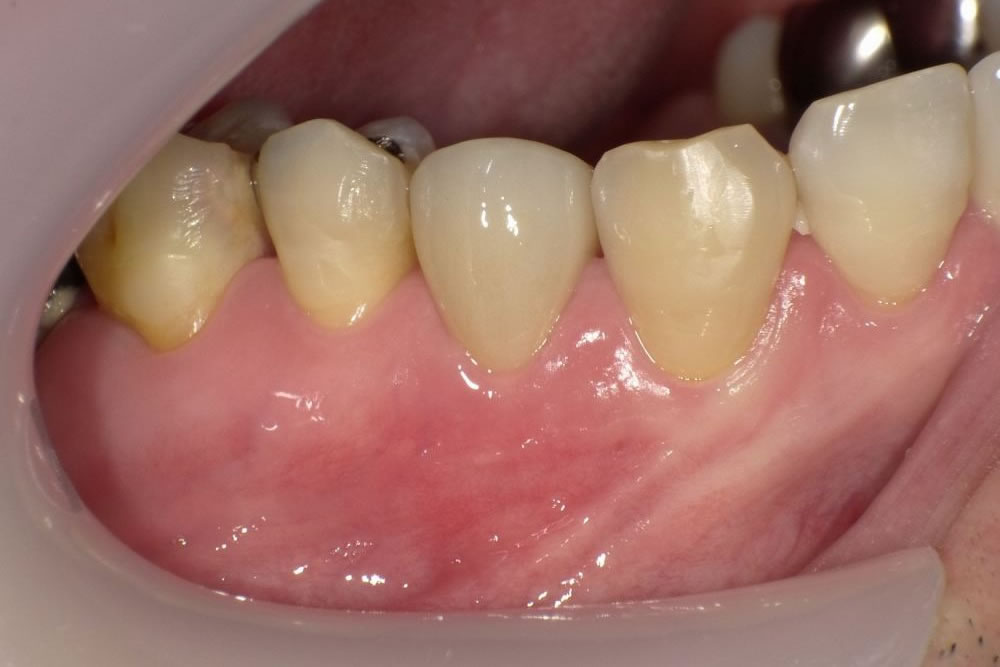

▲3週間の待機期間後からは、仮の歯を被せて噛み始めてもらいました。適度な噛む刺激が加わることで、抜歯によって多少損なわれた歯根膜の再生が、より活性化され、元通りの正常な組織への復活が促進されていくと考えられています。この状態で数週間から数ヶ月間、経過観察をします。写真のとおり、治療前に腫れていた歯茎も治りました。

▲問題がなければ最終的に被せるクラウンの型どりを行い、セラミックの歯を装着して治療を終了します。咬合面側から見たアングルです。歯を抜くことにならずに患者様も満足、私も歯科医師として接着再植治療には大変やりがいを感じています。